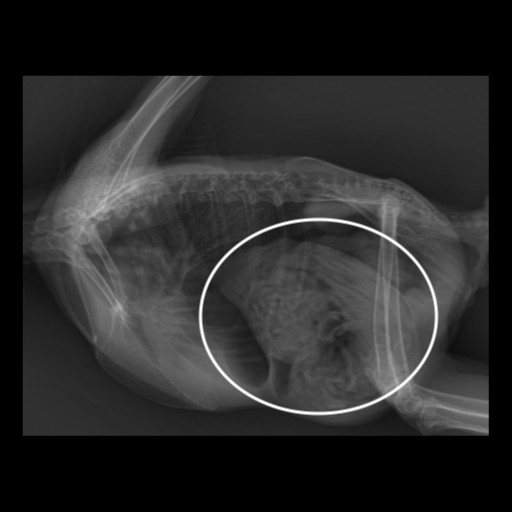

レントゲンを撮影してみると、胃の部分に異物を疑う陰影(写真の白枠)が見つかりました。

靴下を食べてしまったメンフクロウの紹介です。

前日の夜から元気・食欲の低下があり、靴下を食べたかもとのことで来院されました。

来院時かなり具合悪そうで、触診時には、腹部に固いものを触り、脱水もある状態でした。